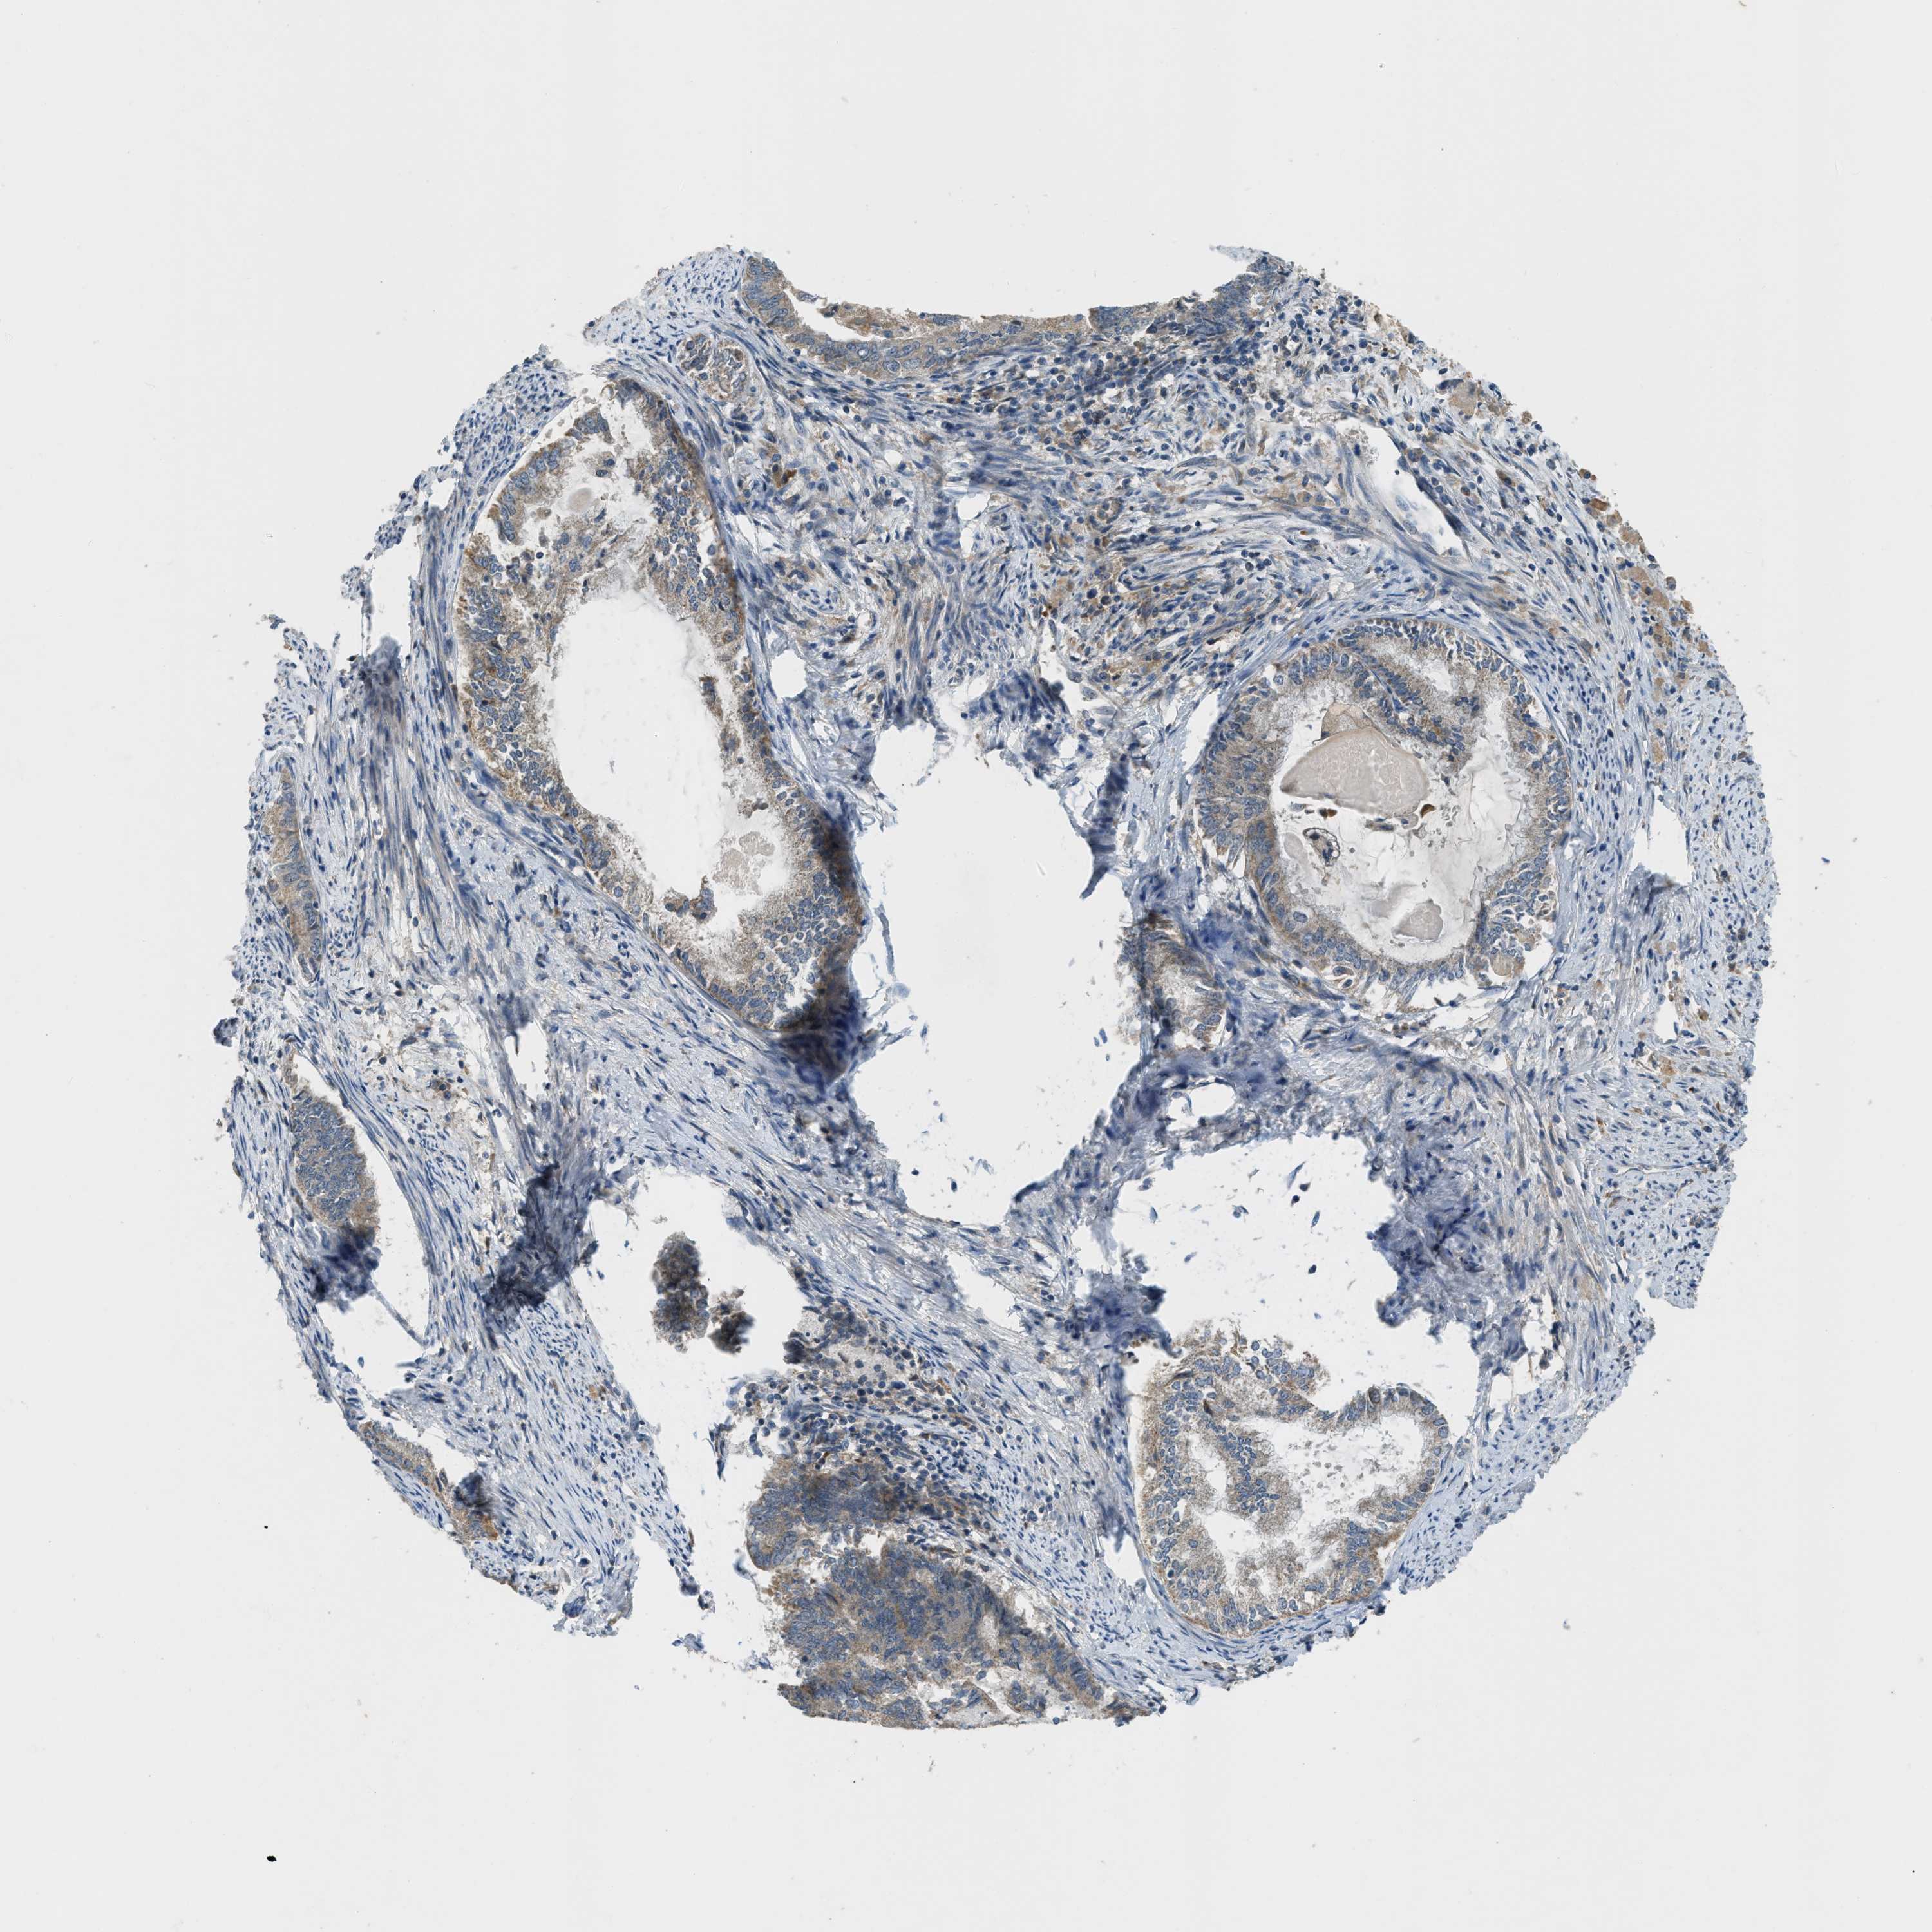

ENDOMETRIAL CANCER - Protein expressioni

A mouse-over function shows sample information and annotation data. Click on an image to view it in a full screen mode. Samples can be filtered based on level of antibody staining by selecting one or several of the following categories: high, medium, low and not detected. The assay and annotation is described here.

Note that samples used for immunohistochemistry by the Human Protein Atlas do not correspond to samples in the TCGA dataset.

Antibody stainingi

Antibody staining in the annotated cell types in the current human tissue is reported as not detected, low, medium, or high, based on conventional immunohistochemistry profiling in selected tissues. This score is based on the combination of the staining intensity and fraction of stained cells.

Each image is clickable and will lead to virtual microscopy that enables deeper exploration of all samples and also displays staining intensity scores, fraction scores and subcellular localization as well as patient and tissue information for each sample.

Antibody HPA018124

Staining

High

Medium

Low

Not detected

Intensity

Strong

Moderate

Weak

Negative

Quantity

>75%

75%-25%

<25%

None

Location

Nuclear

Cytoplasmic/membranous

Cytoplasmic/membranous,nuclear

Adenocarcinoma, NOS

Adenoma, NOS